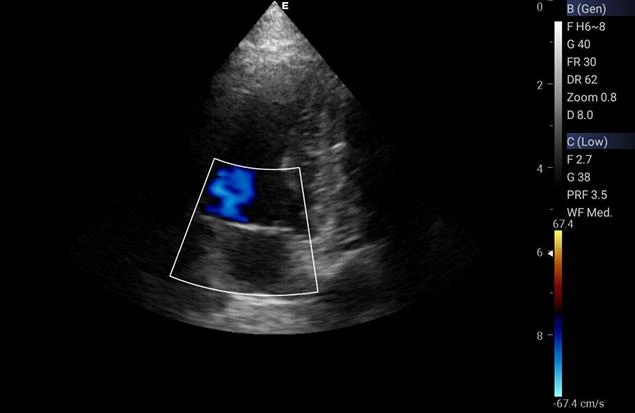

O ecocardiograma é um exame não invasivo e indolor, que utiliza ultrassom para avaliar o coração de animais. Ele fornece informações detalhadas sobre a estrutura e função cardíaca, sendo essencial para o diagnóstico de diversas doenças cardíacas em pets.

A realização de um ecocardiograma em animais é fundamental para identificar precocemente problemas cardíacos, como doenças valvulares, cardiomiopatias e defeitos congênitos.

Com esse exame, é possível orientar o tratamento adequado e melhorar a qualidade de vida do animal.

1. Precisão no Diagnóstico: O ecocardiograma oferece imagens em tempo real do coração, permitindo uma avaliação detalhada e precisa da função cardíaca;